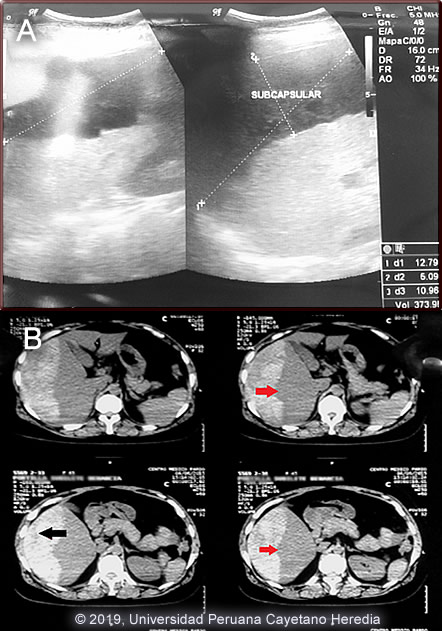

Diagnosis: Subcapsular liver hematoma due to Fasciola hepatica infection (acute phase)

Subcapsular liver hematoma is a rare complication of acute fascioliasis. Very few cases have been reported in the medical literature [Am J Trop Med Hyg 2019;100(3):588; Clin Infect Dis 2011;52(9):1137; Rev Gastroenterol Peru 2003;23(2):142]. While most of these cases required only medical treatment and careful clinical observation with regular hemoglobin measurements, some patients developed hemodynamic instability and required surgical intervention.